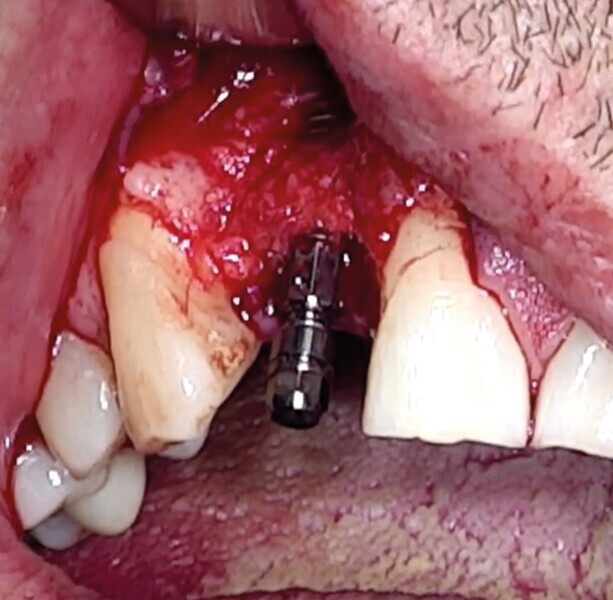

Dans certaines situations cliniques, l’étude radiologique tridimensionnelle montre un volume osseux exploitable en position de 18 ou 28. Il est alors aisé de réaliser le prélèvement au trépan, sur ces sites habituellement larges. Toute la pertinence dans ce cas est de le réaliser à travers la gencive kératinisée et obtenir ainsi une carotte ostéo-gingivale (Fig. 22). De ce fait, il ne faut pas faire d’incision ou de lambeau pour ouvrir l’accès au trépan. Le geste devient extrêmement rapide mais nécessite une bonne connaissance anatomique, une excellente analyse de la planification 3D, puis un bon repérage clinique.6

Pour connaître la profondeur de trépanation, il suffit d’enfoncer la sonde parodontale et de mesurer l’épaisseur de gencive sur l’os. En y ajoutant 4 mm, la profondeur finale est obtenue pour avoir suffisamment d’os. Une fois la carotte ostéogingivale prélevée (Figs. 23 et 24), il ne faut pas séparer l’os de la gencive, mais réduire l’épaisseur gingivale en supprimant la partie kératinisée (Fig. 25). Un implant cylindroconique (Straumann BLT 3,3 SLActive Roxolid) est parfaitement ancré (Fig. 26). La carotte d’os et sa gencive toujours adhérente, sont alors impactées transversalement à l’implant (Fig. 27). La partie osseuse spongieuse est au contact de l’implant, pendant que le conjonctif qui y est attaché, est utilisé comme un greffon conjonctif enfoui sous le lambeau vestibulaire.